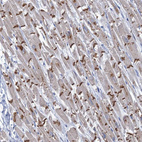

Immunohistochemical staining of human Cerebral cortex shows strong granular cytoplasmic positivity in neuronal cells